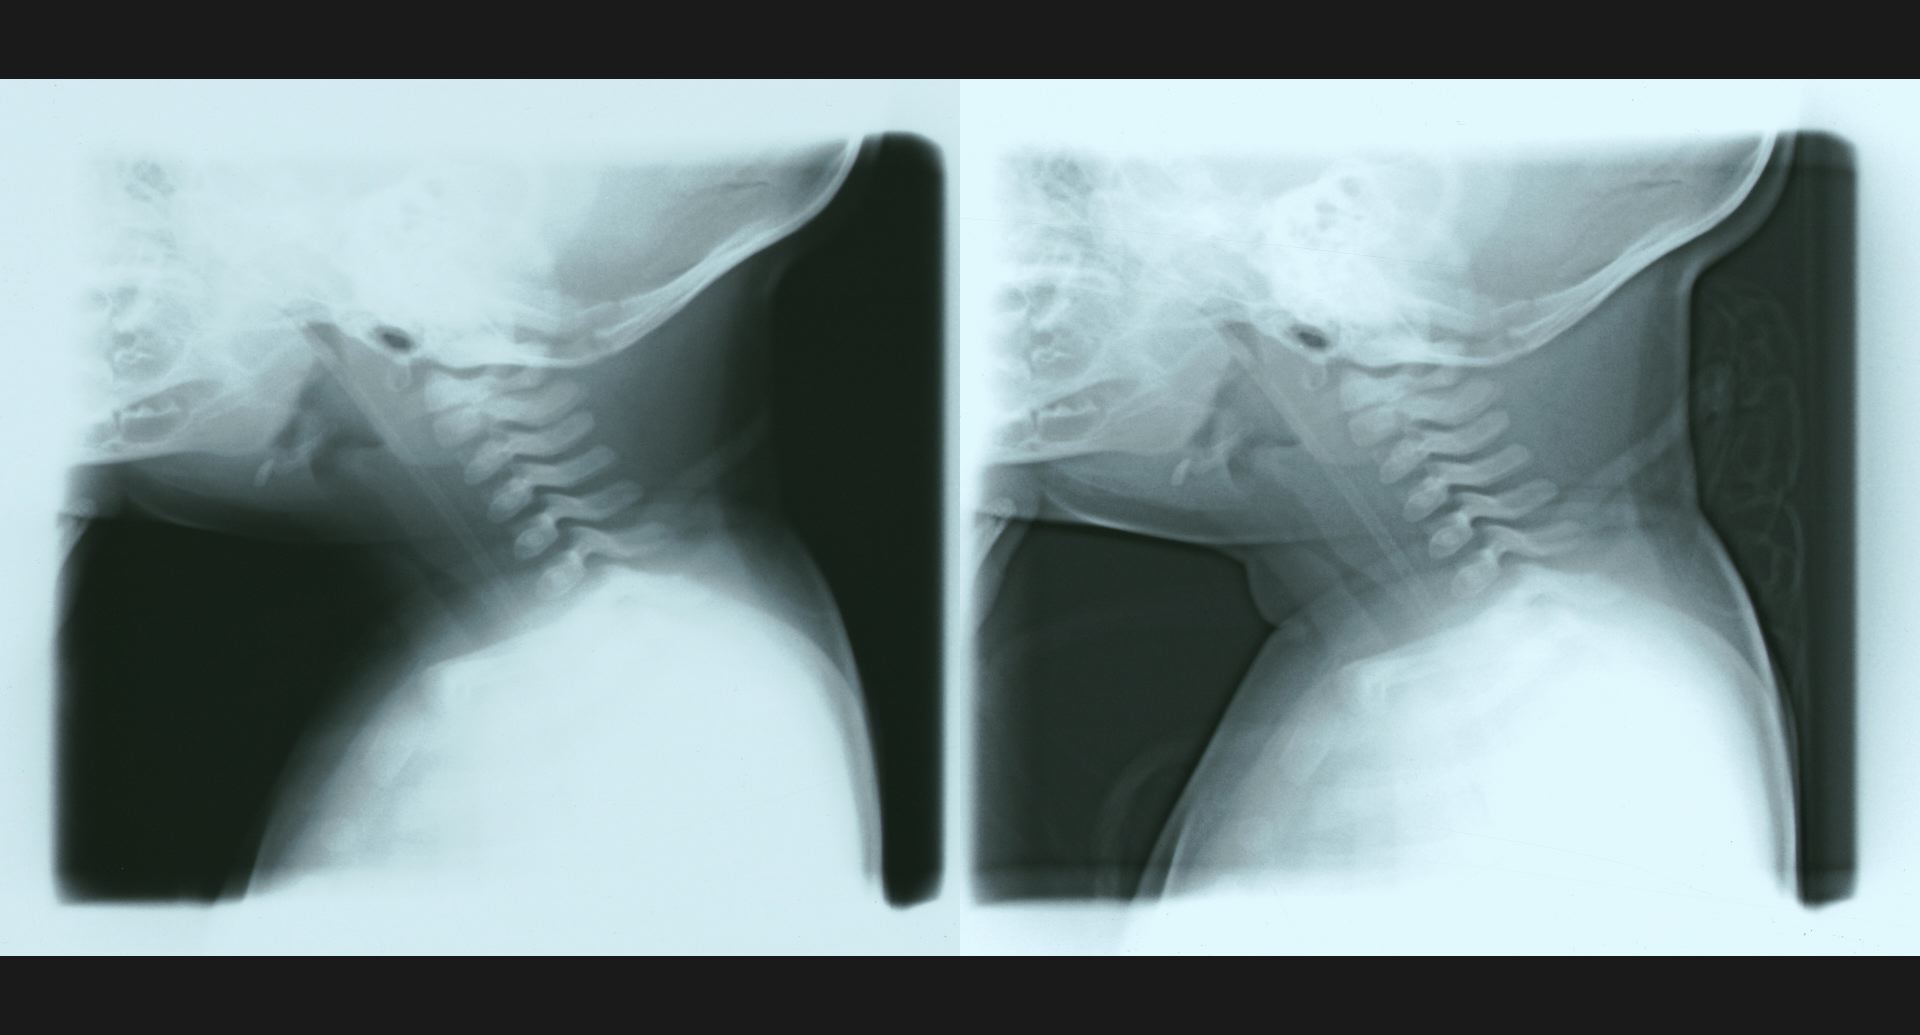

fig.14(77KB)

:Phantom discdisc内の透亮像。spur。